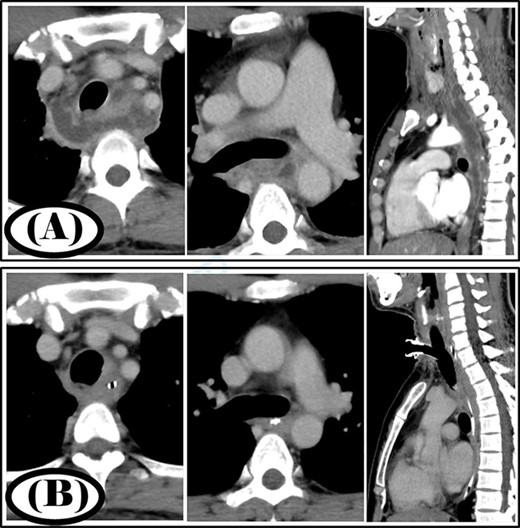

A 77-year-old woman had a chief complaint of sore throat and was diagnosed with a retropharyngeal abscess. Cervicothoracic computed tomography (CT) showed that the infection had spread to the mediastinum (Fig. 1A). The patient was diagnosed with type IIB DNM. Cervical drainage and mediastinal drainage through the cervical approach were performed on the day of admission. Staphylococcus epidermidis, Streptococcus mitis and Acinetobacter lwoffii were detected in the mediastinal abscess cavity. The patient was administered ampicillin/sulbactam at 12 g/day for 3 weeks. Continuous irrigation with saline (2 l/day) was initiated immediately post-surgery. The duration of irrigation, drainage and hospital stay were 4, 10 and 30 days, respectively. Four weeks post-surgery, cervicothoracic CT showed no abscess cavity and the infection had improved (Fig. 1B).

Case 1: pre- and post-treatment cervicothoracic CT; (A) pre-operative cervicothoracic CT and (B) cervicothoracic CT 4 weeks after treatment.